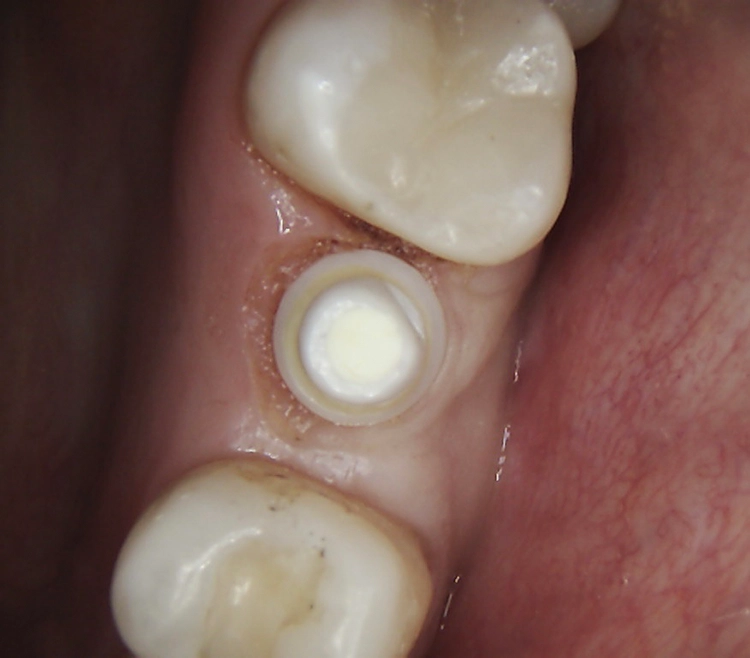

Abb. 2: Repräsentativer Fall von ABH Grad B Septus Typ II. a) Ansichten vor der Installation. Röntgenaufnahme der periapikalen Läsion an einem wurzelkanalbehandelten Molaren und klinische Ansicht der Typ-II-Socket nach der Extraktion. b) Die Ansichten nach der Installation zeigen das Implantat innerhalb des interradikulären Septums und das über dem Implantat platzierte A-PRF. c) Nachuntersuchungen nach 10 Tagen bzw. 2,1 Monaten. Die Röntgenaufnahme zeigt die Knochenbildung zwischen der Sinusmembran und dem apikalen Teil des Implantats. d) Jüngste Nachuntersuchung nach Einsetzen der Prothese.

Abb. 3: Repräsentativer Fall von Grad A Typ I. a) Präoperative Ansicht. Röntgenbild der periapikalen Läsion an einem wurzelkanalbehandelten Molaren. Die Höhe des Alveolarknochens zeigt Grad A an. b) Klinische und radiographische Ansicht der Implantatinsertion unter Verwendung einer Einheilscheibe mit großem Durchmesser (6×8 mm). A-PRF wurde um das Implantat und unter der Scheibe platziert. c) Nachuntersuchung nach 5,9 Monaten vor und nach der Zementierung und Aufbereitung. d) Jüngste Nachuntersuchung nach Einsetzen der Prothese

Bei dem balkonförmigen Implantat blieben die Alveolarkämme und der Kronenansatz erhalten (Abb. 4c und d). Der Spalt zwischen dem Implantat und der bukkalen Lamelle wurde mit A-PRF und einem Kollagenblock aufgefüllt, so dass keine zusätzliche Knochenaugmentation erforderlich war. Zusätzlich wurden PRF-Matrizen um, über, unter und neben dem Implantat im Knochen-Implantat-Raum positioniert (Abb. 1 bis 4b). Außerdem kam eine optionale Einheilscheibe (6 x 8 mm) zum Einsatz, um das Kollagen und die PRF zu sichern (Abb. 3b). Die Implantate zeigten bei einem Drehmoment von 35 Ncm Stabilität, welche mit dem Periotest-Gerät von Medizintechnik Gulden getestet wurde. Die Werte des Implantatstabilitätstests, die im Bereich von –8 bis 0 lagen, wurden als ideal für die Belastung angesehen (Tab. 3).

Die SDS-Zirkoniumdioxidimplantate wurden mit zementierten Pfosten weiter aufbereitet (Abb. 1d, 3 und 4c) und nach 4,74 + 0,95 Monaten Einheilzeit mit endgültigen Kronen versorgt. Die Balkonform ermöglichte ein natürliches Emergenzprofil, das die definitiven Kronen wie die Standardform ausrichtete sowie die Gesundheit des Weichgewebes und die Osseointegration förderte. Bei jeder Nachuntersuchung wurden Stabilität des Implantats, Zustand des umgebenden Gewebes und Vorhandensein von Zahnstein beurteilt.